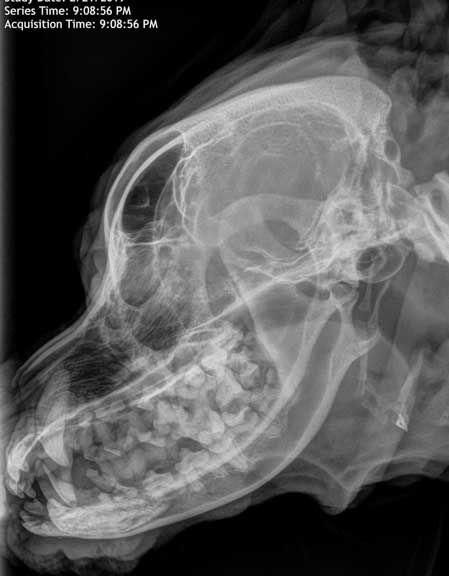

Dog skull x-ray to look at mandible (jaw).

Radiographs of the skull to look at the jaw help in the diagnosis